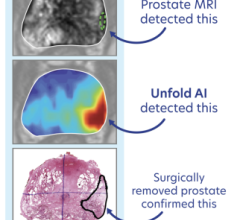

The designation is based in part on three-year follow-up data from a Phase III prospective, randomized clinical trial involving the use of SpaceOAR hydrogel, a technology developed by Augmenix to reduce the risk of rectal injury in men receiving prostate cancer radiation therapy (RT) by acting as a spacer that pushes the rectum away from the prostate during treatment.

SpaceOAR hydrogel reduces rectal injury in men receiving prostate cancer radiation therapy by acting as a spacer – pushing the rectum away from the prostate. This space between organs decreases the radiation dose to the rectum and other organs at risk (OAR). Earlier this year, Augmenix announced published data from their prospective, randomized clinical trial showing that patients treated with SpaceOAR hydrogel prior to prostate cancer radiotherapy demonstrated significant rectal (bowel), urinary and sexual benefits through three years of follow-up.